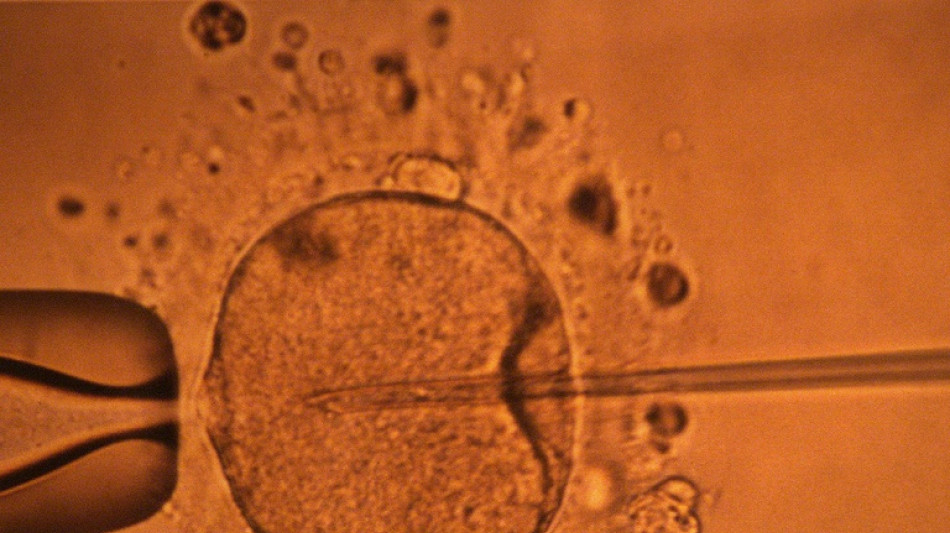

Un estudio apoya hipótesis de disminución mundial de concentración de espermatozoides / Foto: MARCEL MOCHET - AFP/Archivos

La concentración de espermatozoides, uno de los factores de la fertilidad masculina, disminuyó significativamente en todo el planeta en las últimas décadas, según un estudio publicado el martes.

"La concentración de espermatozoides disminuyó significativamente entre 1973 y 2018", resumen los autores de este trabajo publicado en la revista Human Reproduction Update y realizado mediante la compilación de unos 40 estudios previos.